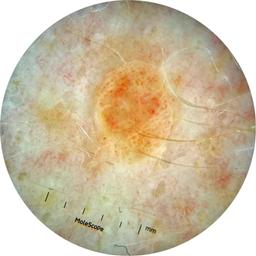

ISIC_3176953

diagnosis_1 Malignant

diagnosis_2 Malignant adnexal epithelial proliferations - Follicular

diagnosis_3 Basal cell carcinoma

image_type dermoscopic